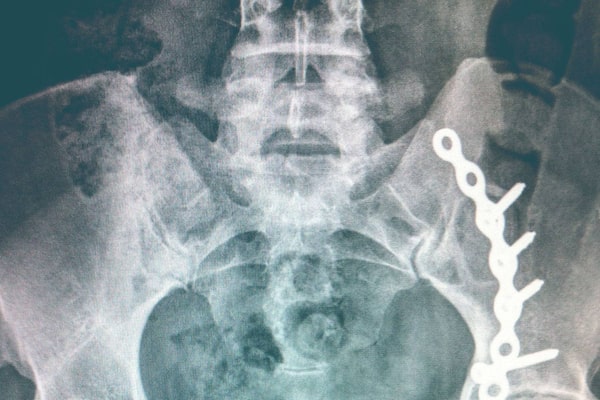

Stacey Taylor’s hip, shown in this x-ray from a previous story, was damaged in a car accident, leaving her in a wheelchair for months. A doctor assessing her claim for her insurance company concluded that her injuries did not warrant long-term benefits.The Globe and Mail